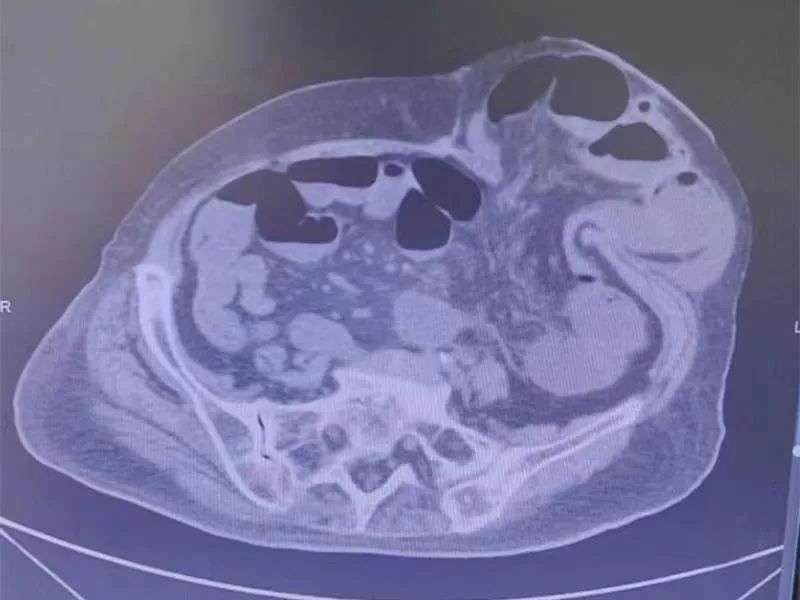

7月13日,王奶奶腹痛腹胀加剧,疼痛难忍,伴随恶心、呕吐症状,在家人的陪伴下入住我院普外一科。经检查,该患有造口处肠管嵌顿、肠梗阻、肠造口旁疝,情况紧急。科室根据CT检查了解其疝内肠管情况后,经手法复位,首先解除了肠道梗阻问题,王奶奶症状稍有缓解,也为后续治疗争取了时间,避免了急诊手术可能给高龄老人带来的风险。

肠梗阻问题是解决了,但折磨老人的肠造口旁疝还没解决。老人虽年事已高,但身体还算硬朗,如果不是被疾病如此折磨,完全可以过上舒适的晚年生活。这次王奶奶已经出现造口旁疝肠管嵌顿,疝的大小达到20cm×17cm,日后再次复发的可能性非常大,如再行急诊手术治疗,将对她的生存造成极大影响。